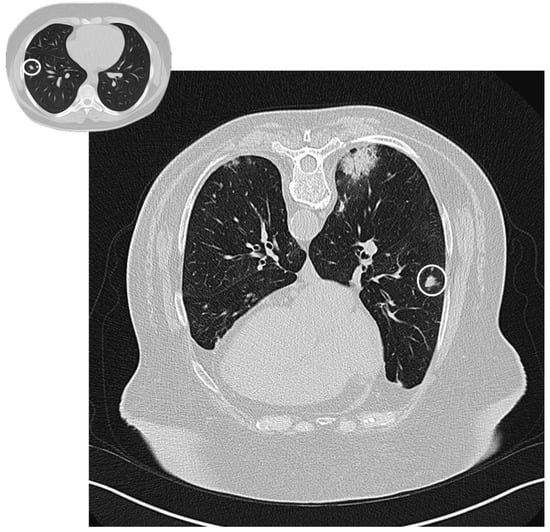

Figure 3. Nodular pattern: peripheral solid nodule (white circles) in a patient affected by COP.

A nodular pattern is seen in 15–50% of patients [25]. Nodules can be solid, part-solid or ground glass, with no specific distribution (sprinkled or peribronchovascular) (Figure 3); they could have spiculated borders, and, because of this appearance, the first suspect is often related to a malignant nature of lesions. If excavated (rare but possible), the nodule can mimic tuberculosis or septic embolism [24]. There are two nodular patterns: the well-defined “acinar” pattern (8 mm in diameter), or the ill-defined micronodular pattern (<4 mm) [20,26]. Acinar-type nodules represent focal areas of organizing pneumonia around plugged bronchioles and may have peribronchovascular or peripheral distribution. The micronodular pattern is an uncommon pattern of OP [20]; micronodulesmay have a peribronchial or centrilobular distribution, resembling a tree-in-bud pattern [26].